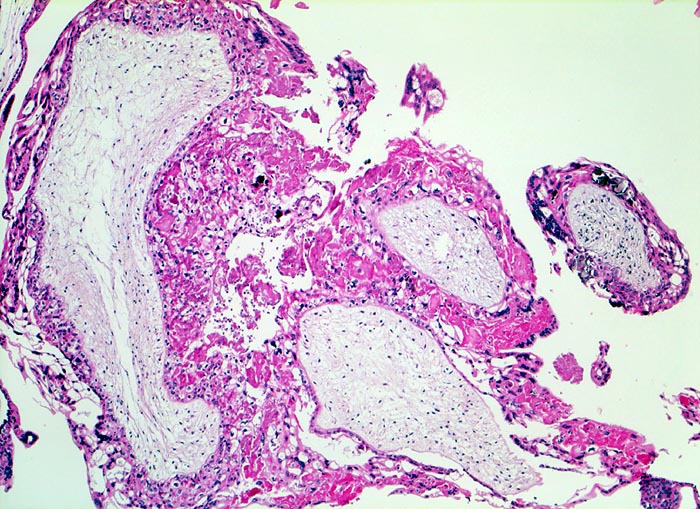

Makroskopisch ist die Plazenta deutlich grösser als erwartet für das Schwangerschaftsalter. Sie ist diffus von bis 2cm grossen Zottenblasen durchsetzt, welche nach Kollaps jedoch der makroskopischen Entdeckung entgehen können. Beim Aufschwemmen in Flüssigkeit entfalten sich die Blasen wieder. Mikroskopisch sind die Zotten aufgrund einer grobblasigen pseudozystischen Hohlraumbildung im Zottenstroma überwiegend grosskalibrig. Im Zottenstroma sind nur ganz vereinzelt Kapillaren nachweisbar. Im Gegensatz zu hydropisch geschwollenen Zotten im Sinne eines Regressionsphänomens zeigen die Zotten bei Blasenmole zusätzlich eine zirkumferentielle Hyperplasie von Synzytio- und Zytotrophoblast mit fakultativer Zellatypie. Bei herdförmiger Mole (> 3725) sind diese Veränderungen nur in einem Teil der Plazentarzotten ausgeprägt.

• Stark vergrösserte und verplumpte Plazentarzotten.

• Hydropisch umgewandeltes Zottenstroma ohne Gefässe mit Ausbildung von pseudozystischen Hohlräumen (Blasen)

• Trophoblastinklusionen und Kerntrümmer im Zottenstroma.

• Überschiessend proliferiertes Trophoblastepithel, teils in der gesamten Zirkumferenz der Zotten mit deutlichen Kernatypien. Kein Embryo.